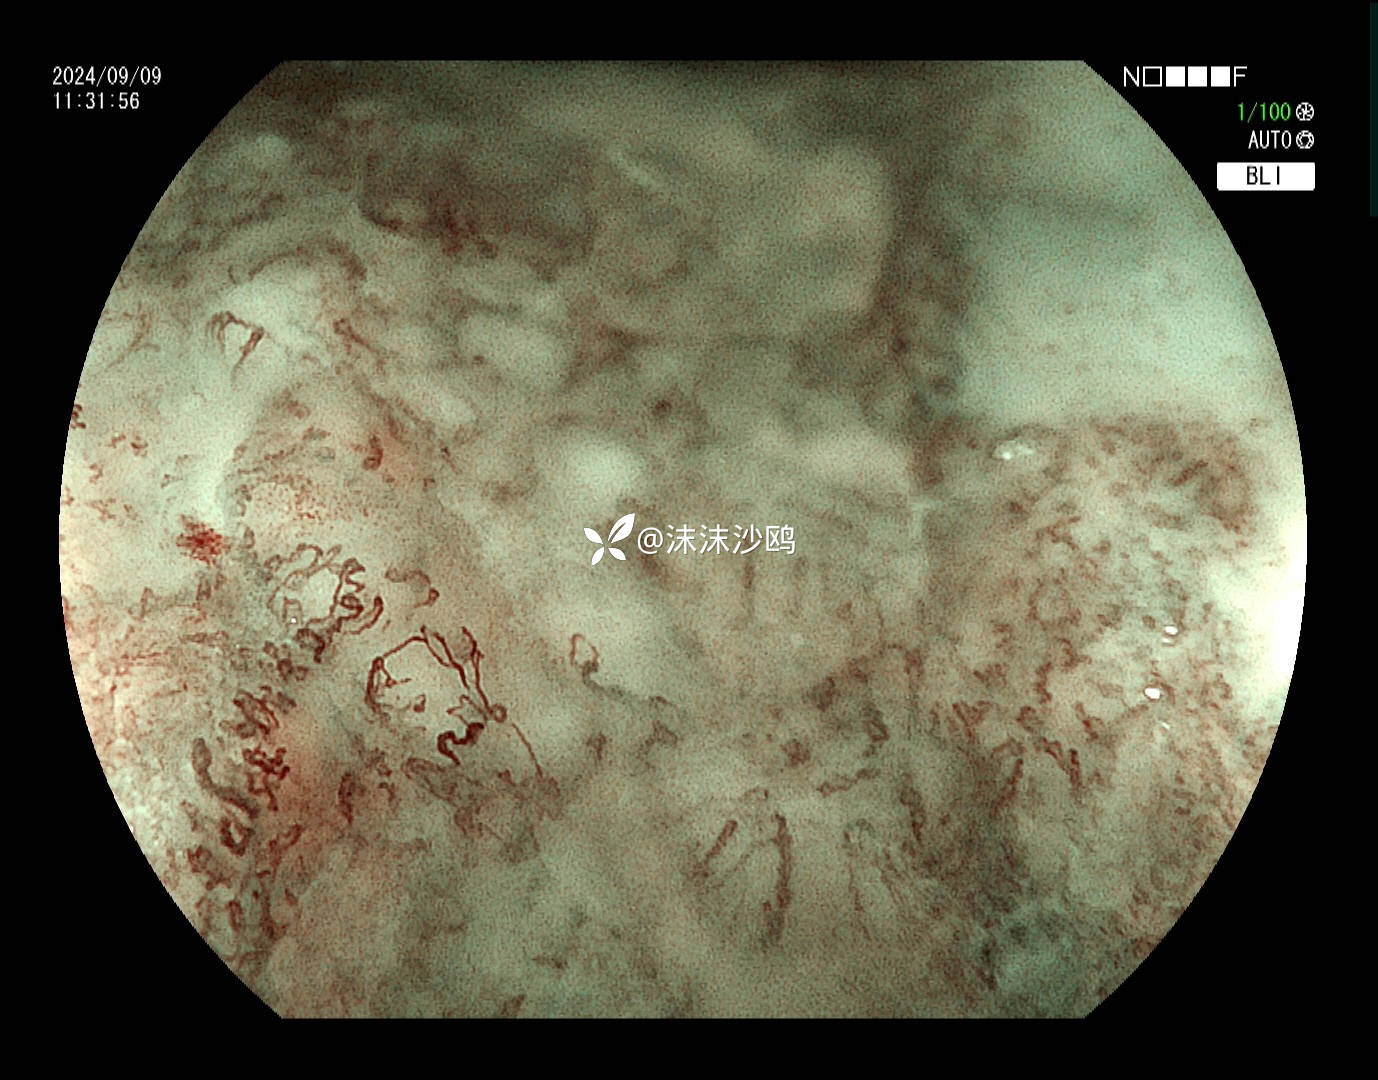

ME

该患者平素无明显症状,吸气注气观察病灶延展性,柔软度可,白光观察粘膜呈现发红粗糙,BLI放大观察呈现明显茶褐色,可见B1型血管,局灶可见紊乱生长的B2型血管,并见AVA区域,感觉小于0.5mm。镜下考虑浸润深度,不超过SM1,应该有内镜下D的可能性。等病理结果,希望符合内镜诊断。